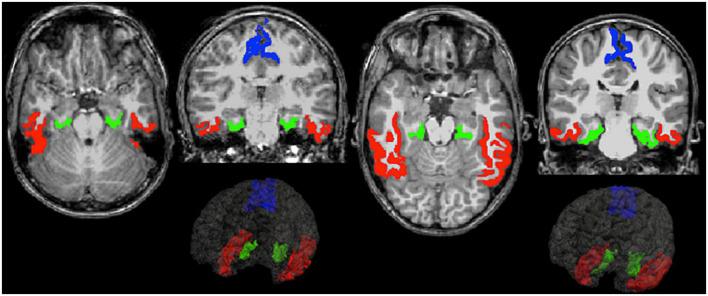

Included adolescents were born very preterm (gestational age < 32 weeks and/or birth weight ≤ 1,500 g) between April 2004 and December 2006 at the Turku University Hospital, Finland. Information on maternal smoking status (yes or no) during pregnancy was collected from medical records and maternal questionnaires before discharge. Adolescents underwent volumetric brain MRI at 13 years of age. Image post-processing was performed with FreeSurfer. Regional volumes, cortical thickness, surface area, and curvature were computed from 33 cortical regions of interest (ROIs). Additionally, volumes were calculated for 18 subcortical regions, as well as for white matter, gray matter, and intracranial volume. We normalized quantified absolute volumes for head size by dividing volumes with corresponding intracranial volumes. false discovery rate (FDR) correction for multiple comparisons across regions was used.

A total of 9/44 (21%) adolescents had been exposed to maternal smoking during pregnancy. No statistically significant differences in absolute volumes were observed between the groups ( > 0.05). Regarding volumes proportional to intracranial volume, the adolescents in the exposed group exhibited smaller gray matter volumes in the inferotemporal (FDR corrected = 0.022) and parahippocampal ( = 0.018) regions compared to the unexposed group. The surface area in the exposed group was also smaller in the parahippocampal ( = 0.046) and postcentral ( = 0.046) regions compared to the unexposed group. No statistically significant differences after correction for multiple comparisons were found for either curvature or cortical thickness between the groups.